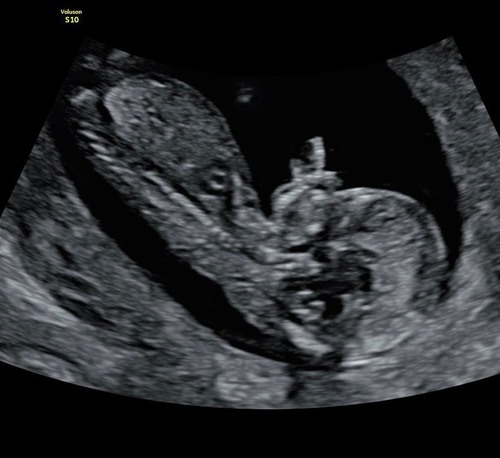

Ik heb ook nog deze foto. Is dit een nub of niet? 😅